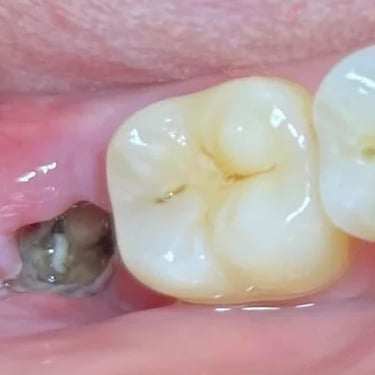

Quiste dentígero

Un quiste dentígero es un saco lleno de líquido que se forma alrededor de la corona de un diente no erupcionado.

Los pacientes pueden notar una hinchazón indolora en la mandíbula.

El tratamiento incluye la extirpación quirúrgica del quiste y, a veces, la extracción del diente involucrado.